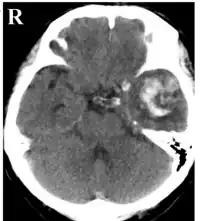

| CT scan showing cerebral contusions, hemorrhage within the hemispheres, subdural hematoma on the left, and skull fractures[1] | |

In terms of the evaluation, computed tomography (CT) is used to identify contusion or laceration.[12]